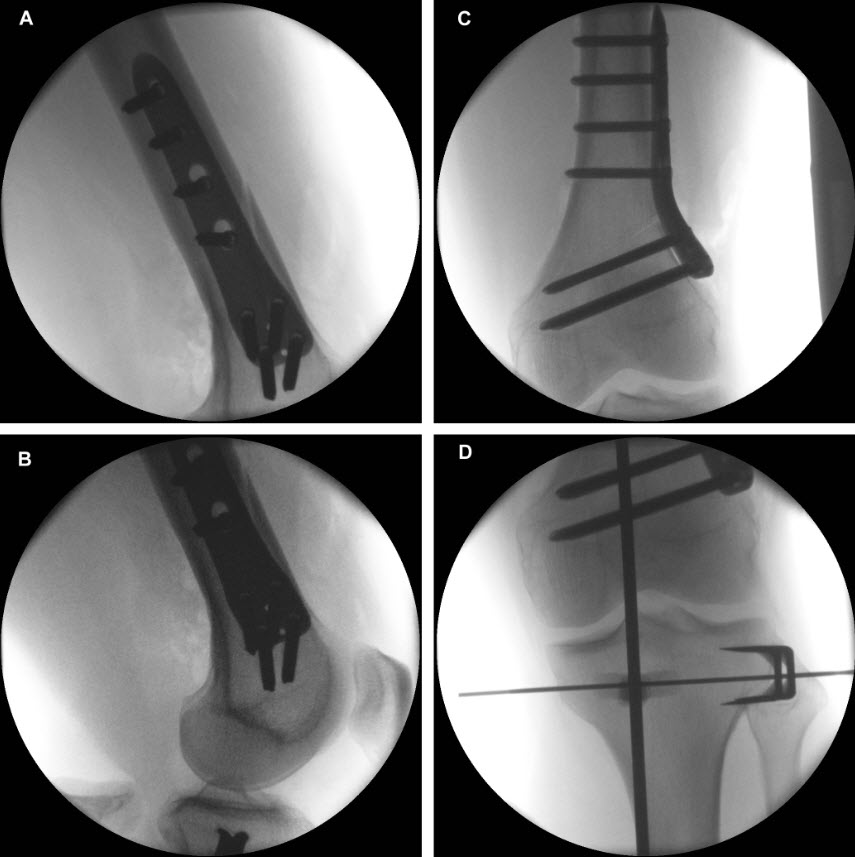

- The 5° slant of the plate helps achieve parallel fixation of the proximal plate to the plateau slope of smaller statured tibia (Fig 2)

- The new plate shape facilitates plate placement towards the medial side, providing support on the medialposterior edge of the tibial plateau. This also functions to help prevent neurovascular damage

caused by possible screw protrusion (Fig 3) - The TomoFix MHT plate is designed to accommodate both small and large oblique osteotomies

- The aiming arm and K-wire guide support the insertion of K-wires to help maintain tibial slope and aim at the hinge points (Fig 5)

- The saw guide allows surgeons to perform biplanar osteotomy under x-ray guidance (Fig 6)